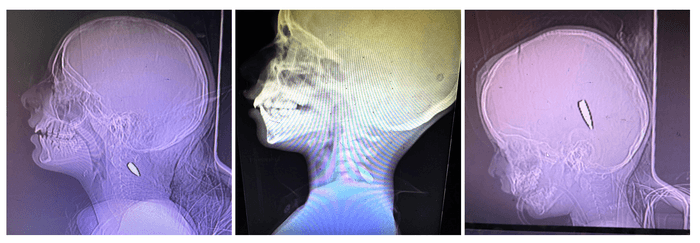

The essay, bylined by trauma surgeon Feroze Sidhwa, includes three photos of X-rays that Mimi Syed—an emergency medicine doctor based in Olympia, Washington—provided to the Times.

“I had multiple pediatric patients, mostly under the age of 12, who were shot in the head or the left side of the chest,” Syed, who worked in Khan Younis from August 8 to September 5, told the newspaper. “Usually, these were single shots. The patients came in either dead or critical, and died shortly after arriving.”